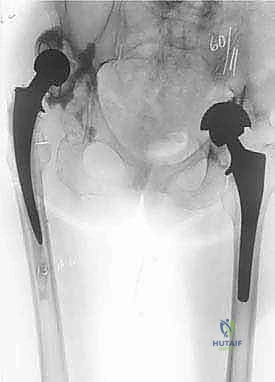

- الأشعة السينية التقليدية (X-rays): صور متعددة الزوايا لتقييم التآكل العظمي، هجرة المكونات، وتحديد تصنيف فقدان العظم (مثل تصنيف Paprosky).

- الأشعة المقطعية (CT Scan): ضرورية للغاية لتقييم مخزون العظم الحُقّي (في الحوض) وتحديد حجم التجاويف العظمية بدقة ثلاثية الأبعاد. تساعد في التخطيط لاستخدام دعامات معدنية أو ترقيع عظمي.

| وجه المقارنة | استبدال مفصل الورك الأولي (Primary THA) | مراجعة مفصل الورك (Revision THA) |

| الهدف الأساسي | علاج خشونة المفصل الطبيعي وتخفيف الألم. | إزالة غرسات فاشلة/معيبة، علاج العدوى، استعادة العظام. |

| حالة التشريح | طبيعي، معالم واضحة، عضلات سليمة غالبًا. | مشوه بشدة، ندوب كثيفة، معالم مفقودة، عضلات ضعيفة. |

| جودة العظام | جيدة إلى ممتازة في معظم الحالات. | غالبًا ما تكون هشة، متآكلة، أو مفقودة جزئيًا. |

| نوع الغرسات | غرسات قياسية (Standard Implants). | غرسات مراجعة متخصصة (سيقان طويلة، كؤوس جامبو، دعامات، ترقيع عظمي). |